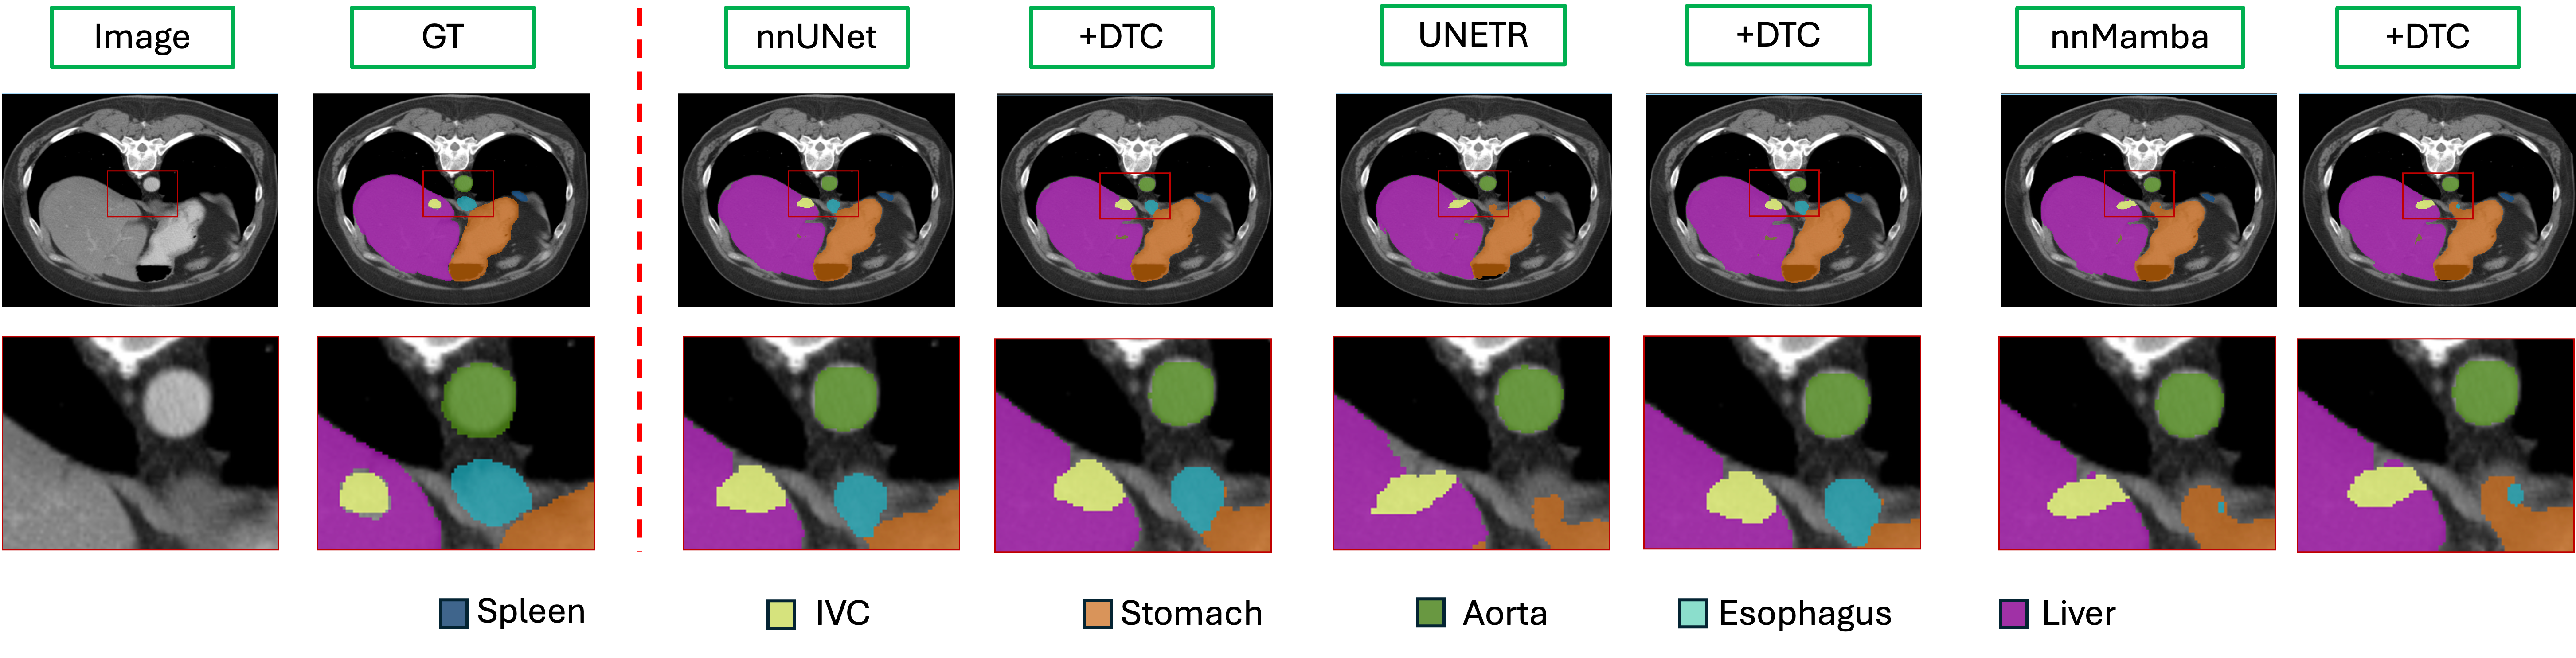

Figure 6: Visualization of the DTC module applied to a 3D segmentation model. The first row shows the 2D segmentation slices, and the second row presents the zoomed-in views of the regions highlighted by the red rectangles. “IVC” is the abbreviation for Inferior Vena Cava.

The experimental results in Table 3 show that DTC provides notable performance improvements for UNETR and nnMamba, while the performance improvement for nnUNet is relatively smaller. This difference may be due to nnUNet not applying a uniform upsampling stride across all dimensions, resulting in limited learning of 3D features in some dimensions. Consequently, the 3D upsampling process approximates a combination of 2D results, which may constrain the deformable structure’s ability to capture full 3D information. This constraint prevents our coordinate generation process from fully leveraging DTC’s potential for enhancing performance. In the Fig. 6, the esophagus was not segmented by UNETR and nnMamba; however, after introducing DTC, it is successfully segmented.